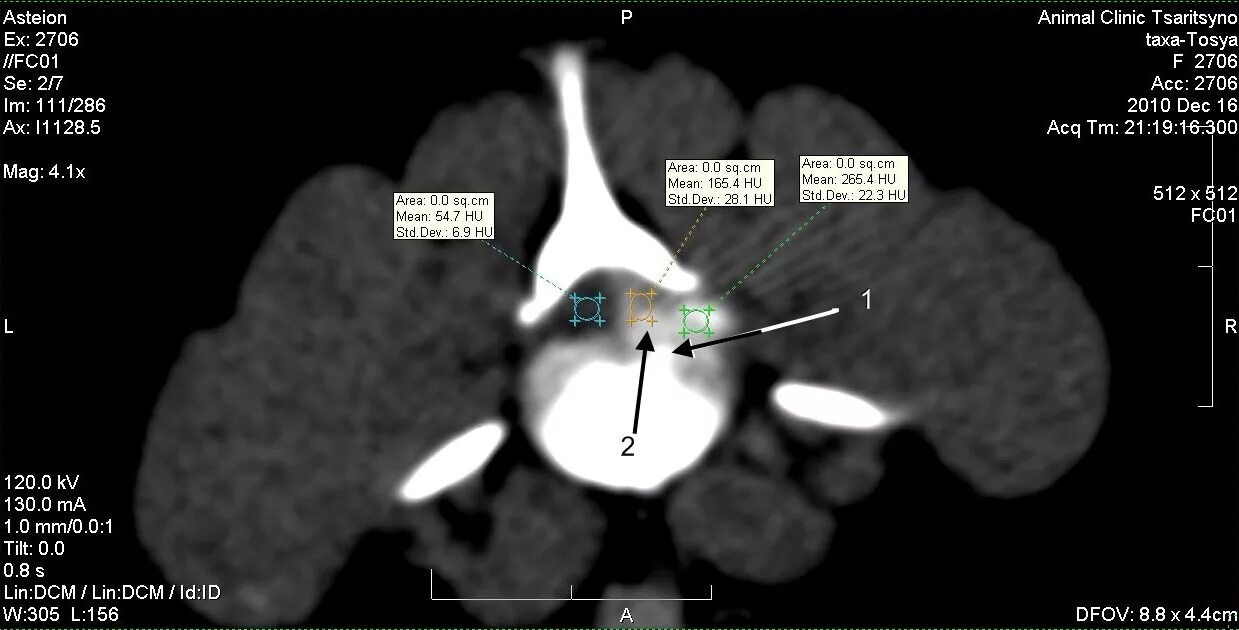

Диагноз грыжа диска